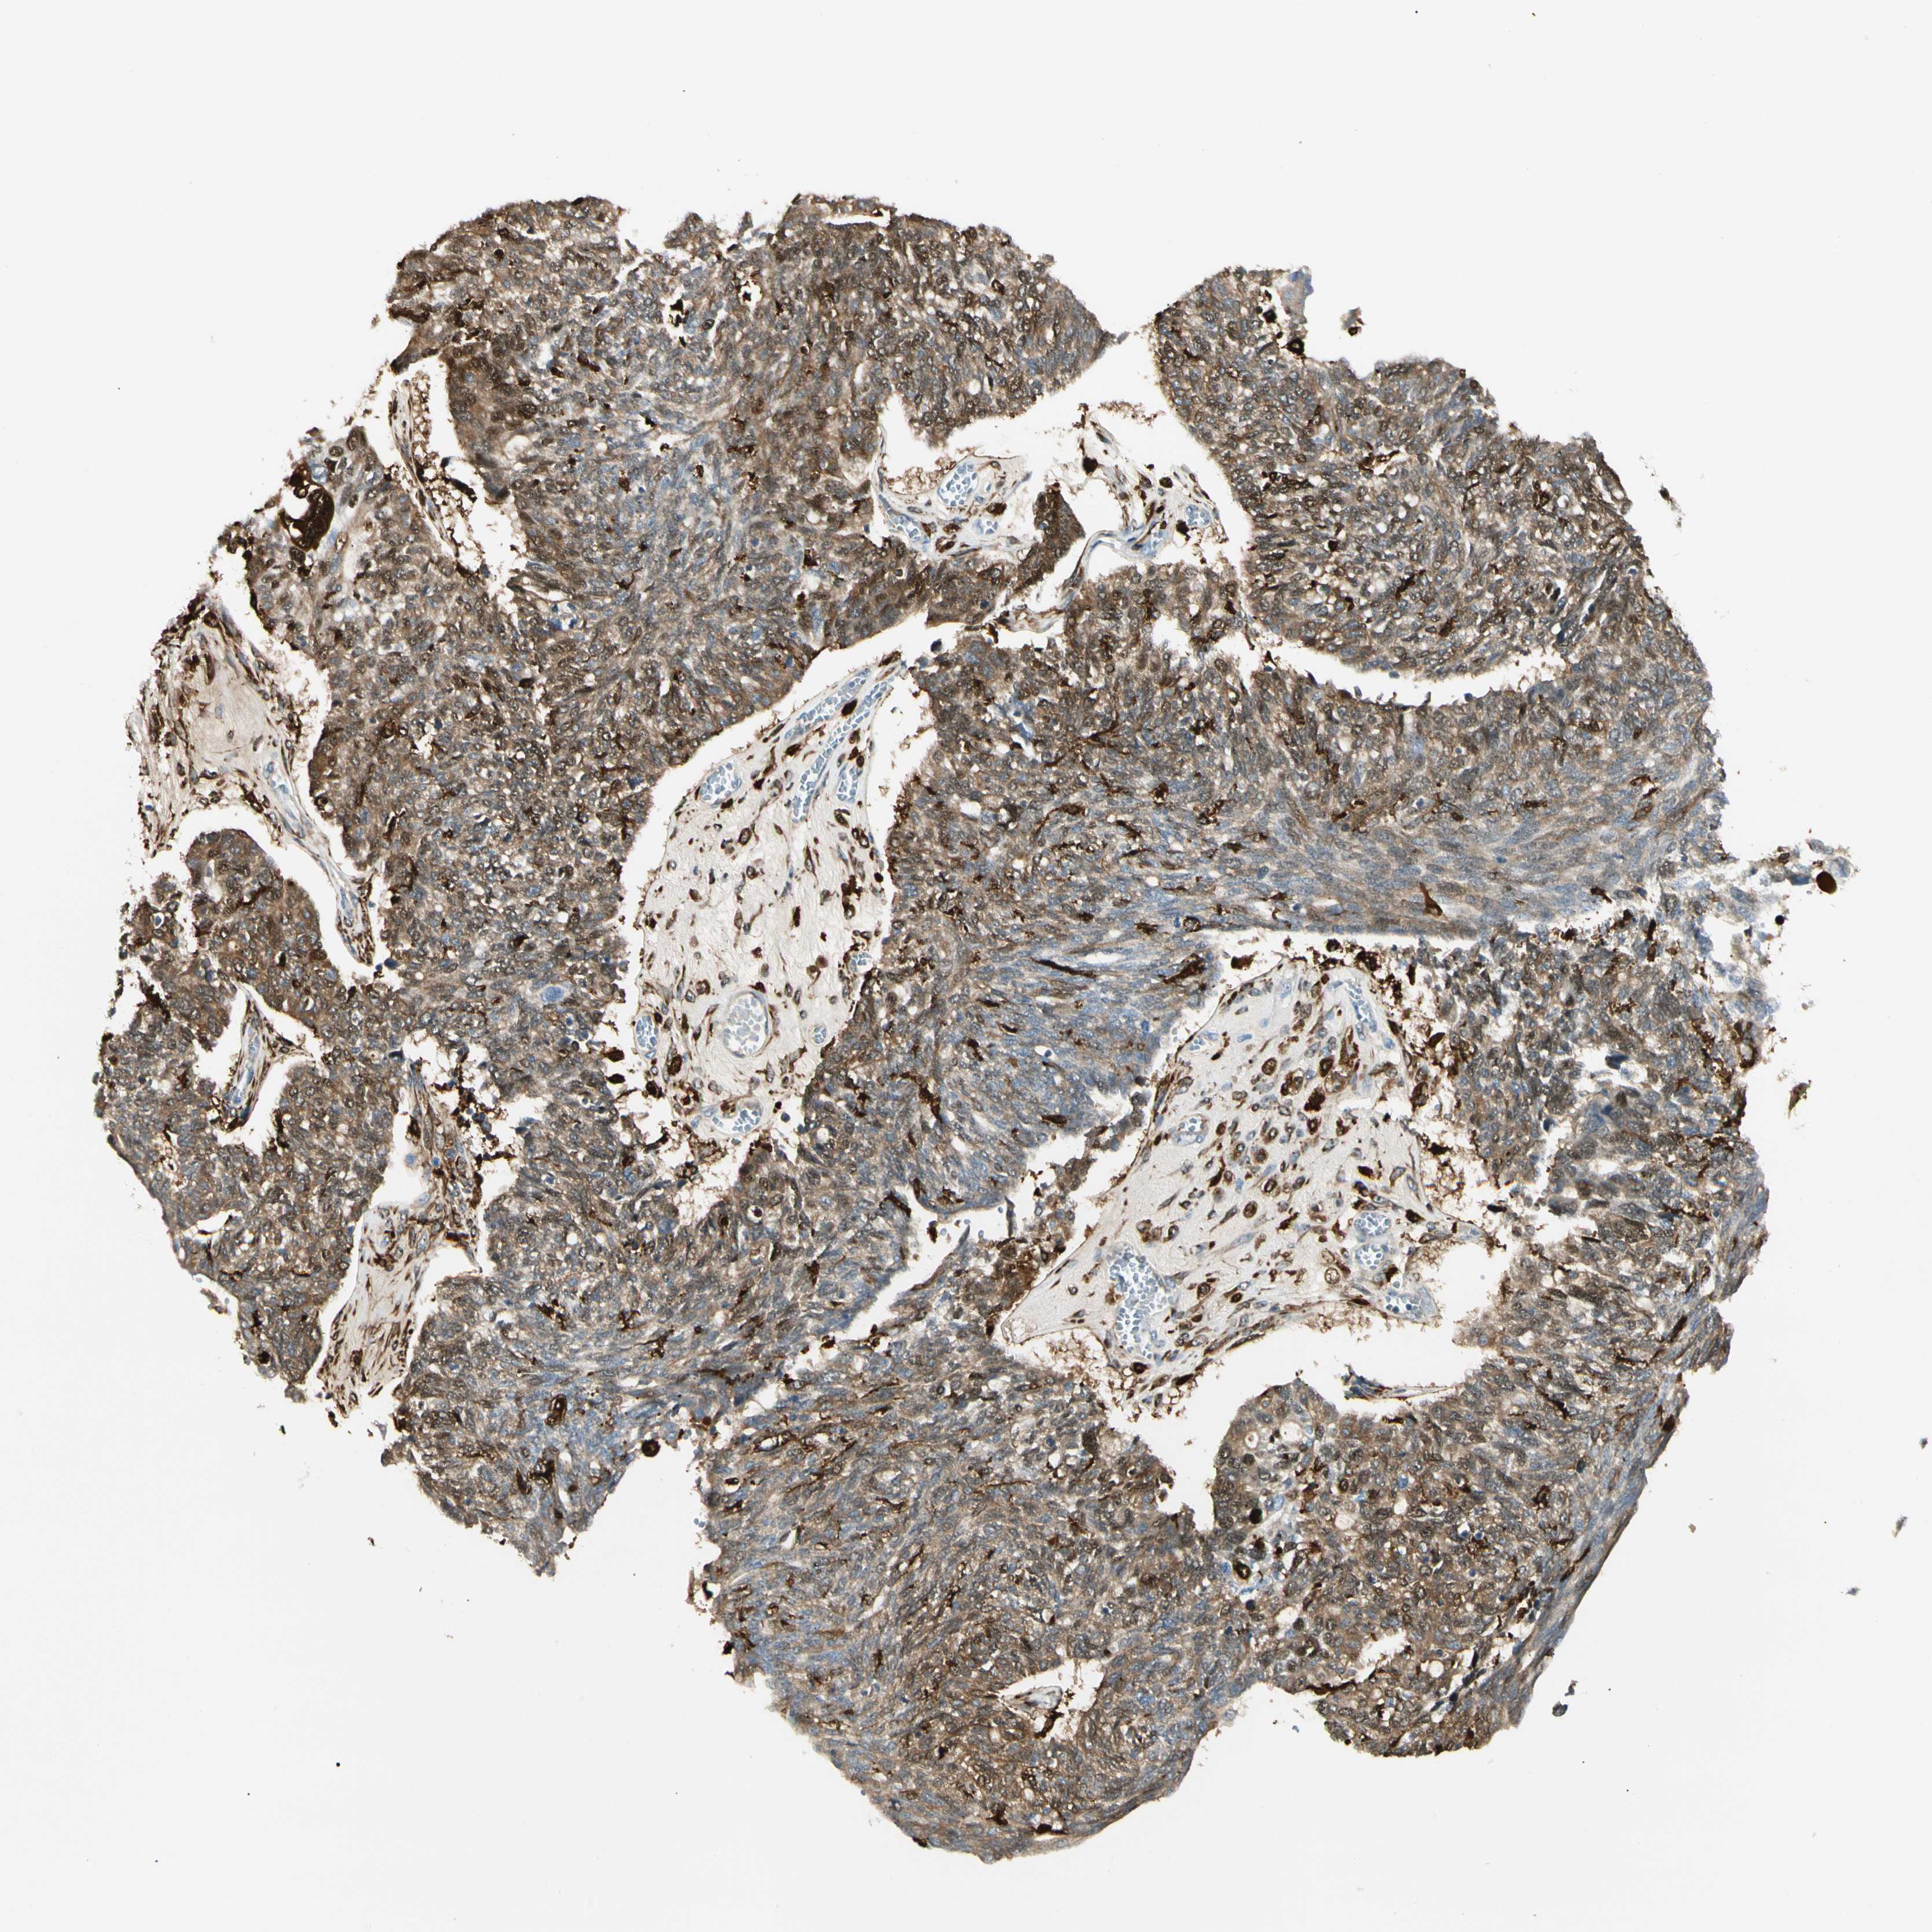

OVARIAN CANCER - Protein expressioni

A mouse-over function shows sample information and annotation data. Click on an image to view it in a full screen mode. Samples can be filtered based on level of antibody staining by selecting one or several of the following categories: high, medium, low and not detected. The assay and annotation is described here.

Note that samples used for immunohistochemistry by the Human Protein Atlas do not correspond to samples in the TCGA dataset.

Antibody stainingi

Antibody staining in the annotated cell types in the current human tissue is reported as not detected, low, medium, or high, based on conventional immunohistochemistry profiling in selected tissues. This score is based on the combination of the staining intensity and fraction of stained cells.

Each image is clickable and will lead to virtual microscopy that enables deeper exploration of all samples and also displays staining intensity scores, fraction scores and subcellular localization as well as patient and tissue information for each sample.

Antibody CAB008623

Cystadenocarcinoma, serous, NOS

Carcinoma, endometroid

Cystadenocarcinoma, mucinous, NOS

Carcinoma, NOS